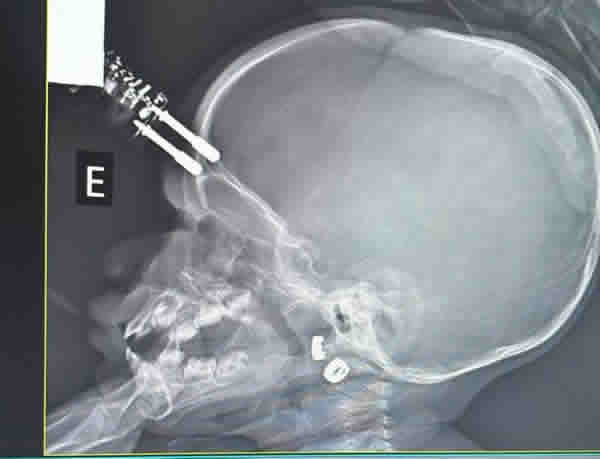

De acordo com o neurocirurgião Bruno Castro, exames de tomografia apontaram que o pino do carregador atravessou o crânio da bebê, o que exigiu a imediata condução da paciente ao bloco cirúrgico. Após o procedimento, a menina permaneceu internada por 36 horas no Centro de Terapia Intensiva (CTI) e, posteriormente, recebeu alta médica, sem apresentar sequelas aparentes.